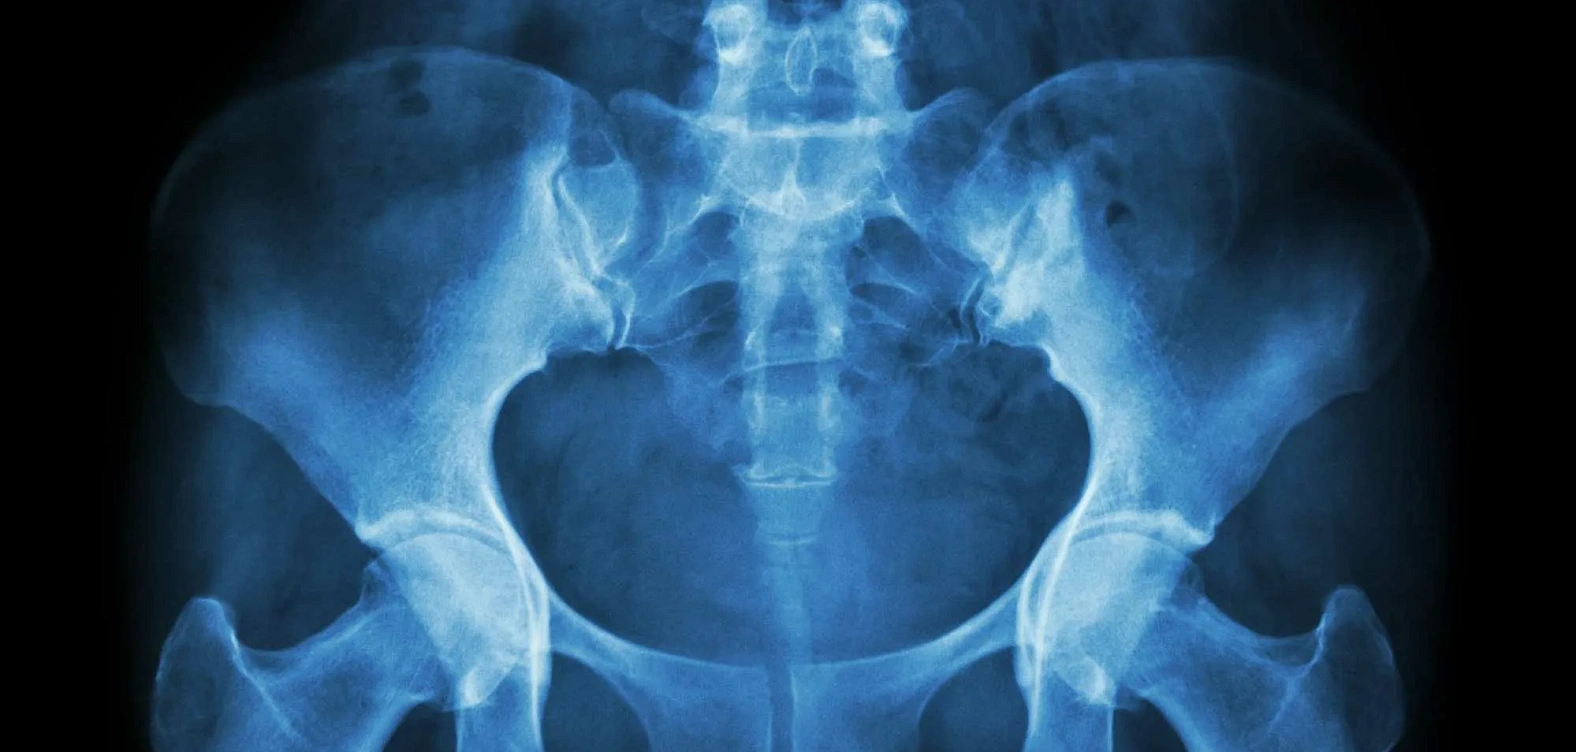

Рентгенография костей таза — это один из наиболее доступных и информативных методов диагностики, позволяющий выявить травмы, воспалительные процессы и дегенеративные изменения в области тазового пояса. Данное исследование часто назначается при болях, ограничении подвижности, подозрении на переломы и патологиях тазобедренных суставов.

Рентгенография тазовой области помогает диагностировать такие патологии, как переломы таза, крестца, копчика и вертлужной впадины, вывихи и подвывихи тазобедренных суставов, дегенеративные изменения (коксартроз, остеоартрит), воспалительные процессы (артрит, остеомиелит), опухолевые образования и кисты, посттравматические изменения, последствия старых повреждений, дисплазию тазобедренного сустава (врождённую или приобретённую).